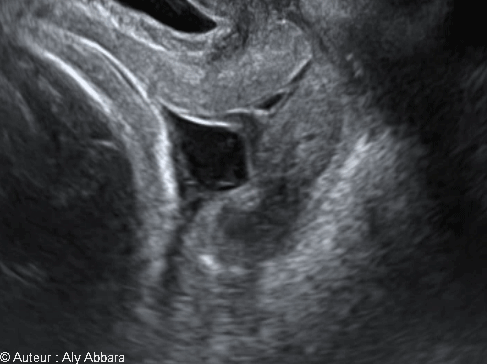

Images échographiques montrant la poche des eaux agissant sur la col utérin sous l'effet des contractions utérines

Sur cette image animée, les membranes amniotiques juxtaposant l'orifice interne du col utérin, sous l'effet de la pression engendrée par les contractions utérines, forment une poche contenant du liquide amniotique ; cette poche pénétré dans le canal cervical après avoir dilaté en premier temps l'orifice interne du col utérin.

Cette action de la poche des eaux sur col utérin est à l'origine des deux phénomènes obstétricaux en début du travail : l'effacement et la dilatation du col utérin.

Un fois la poche des eaux est rompue, c'est la partie fœtale se trouvant en contact avec le pôle inférieur de la cavité utérin (le segment inférieur et le col utérin) qui effacera et dilatera ce col utérin et fera progresser le travail jusqu'à son terme.